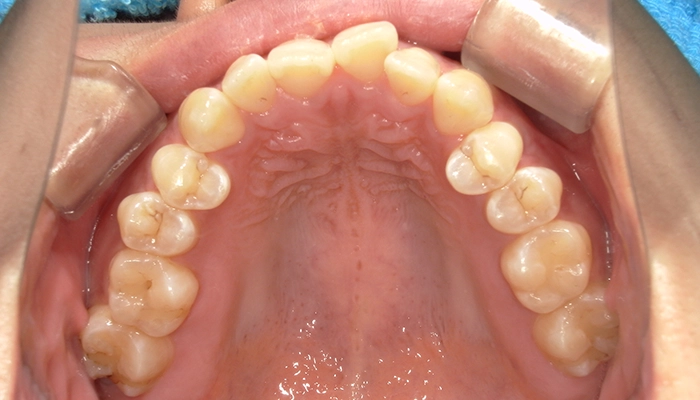

また、当初部分矯正を希望されていましたが、精密検査を行ったところ前歯だけではなく奥歯の噛み合わせの改善も必要でしたので、当院からはマウスピース型矯正装置(インビザライン)による全体矯正をご提案いたしました。

今回の治療では、健康な歯は抜歯していません。抜歯したのは親知らず1本のみです。

治療期間はワイヤー矯正にした際の治療計画予定と比べ、嬉しいことに約1年間も短縮できました。

また、ワイヤー矯正ではインプラントアンカーが必要でしたが、今回のマウスピース型矯正装置(インビザライン)ではインプラントアンカーの埋入は行わず、治療を終えることができました。